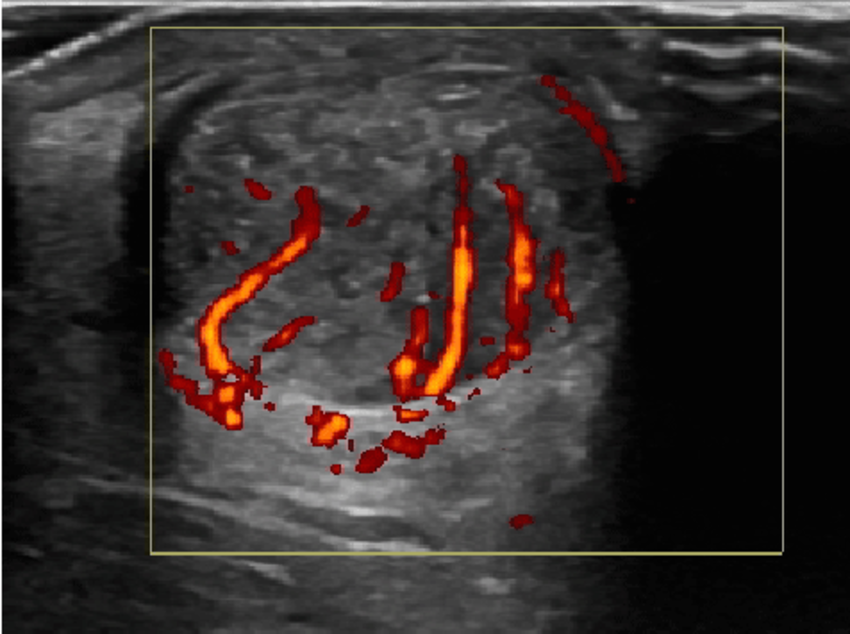

图:跟腱腱病超声横断面 + 多普勒血流信号

这张图展示了跟腱在超声横断面下的表现,有以下几个重点:

低回声区(暗区) 表示腱组织退变、胶原混乱,与慢性腱病的组织改变一致。

彩色多普勒高血流信号 指代新生血管/异常血流,是慢性病变活跃阶段的常见特征,提示代谢较活跃或“代偿性反应”。

这是最常见的慢性跟腱病类型,多见于跑步、跳跃人群。

图:高定义多普勒下的血流增生

这张是纵向视图结合彩色多普勒血流的超声图:

大量异常血流(橘红色) 是慢性腱病的一个超声特征,特别是在中段型跟腱病中更明显。

它不等同于急性炎症的“经典炎症性充血”,但常提示慢性病变组织代谢活跃。